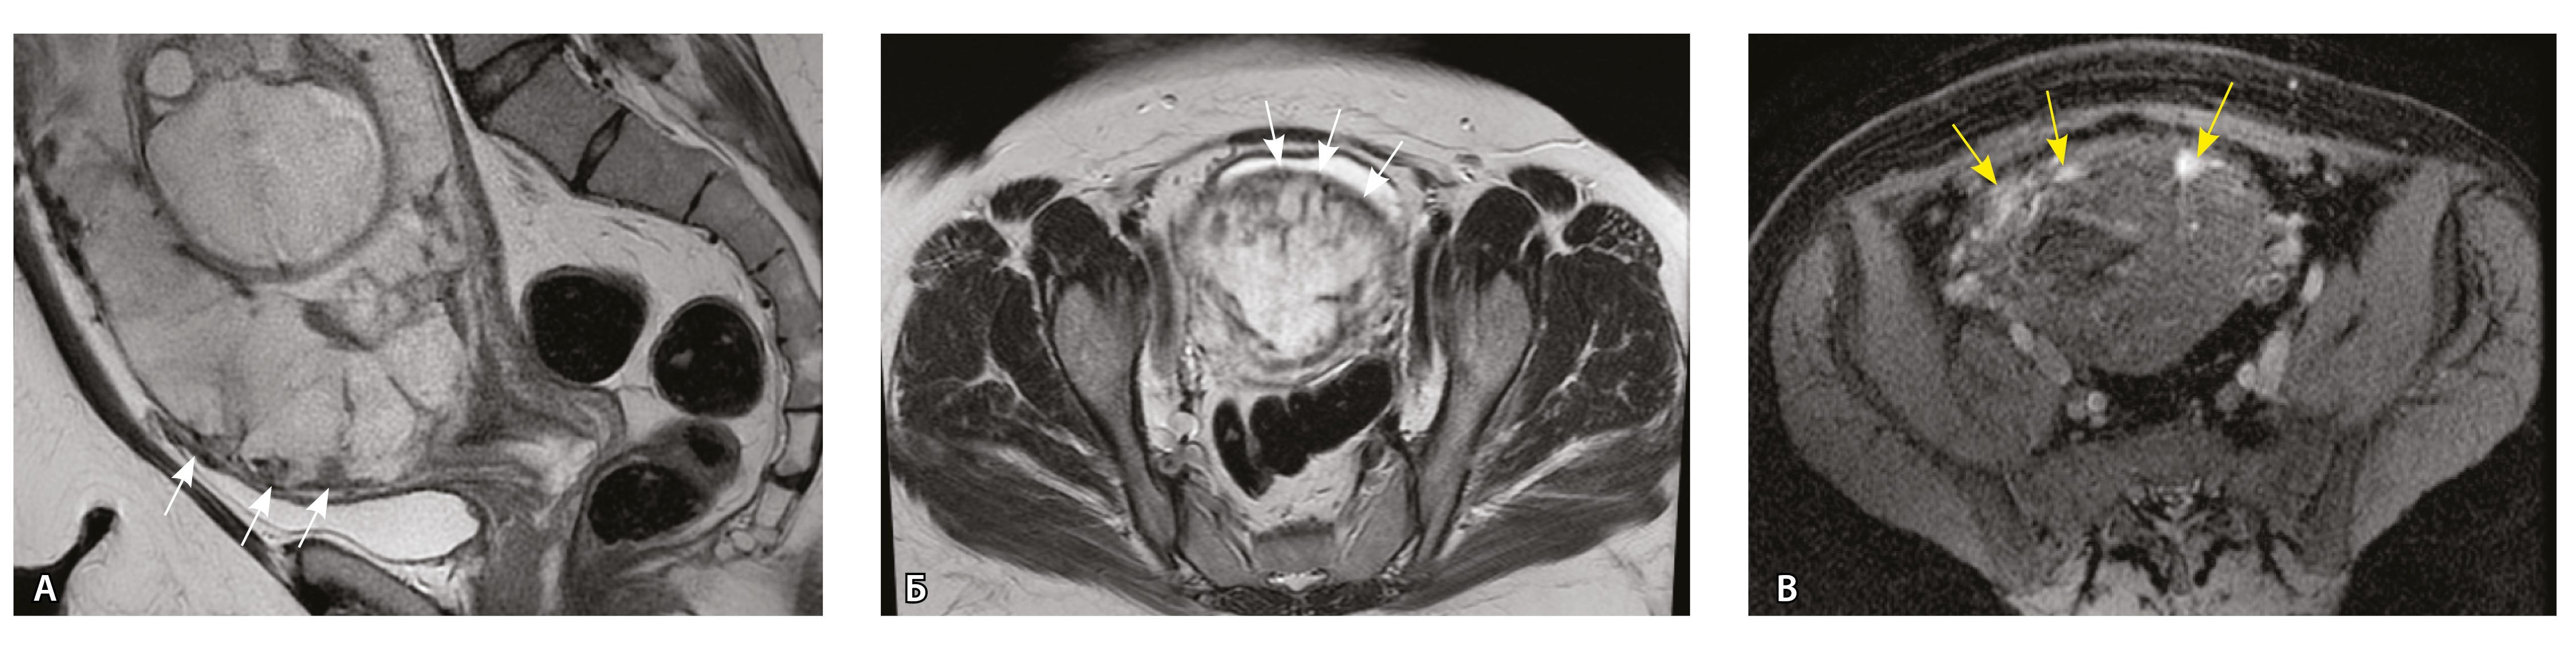

Сосуды 1-го типа. Единичные сосуды в миометрии и пограничных отделах в маточно-плацентарной области (рис. 2).

Рис. 2. Беременность 32 недели, центральное предлежание плаценты без признаков приращения. На магнитно-резонансных томограммах в режиме Т2-взвешенного изображения (Т2ВИ) в сагиттальной плоскости (А) и Т2ВИ с подавлением сигнала от жировой ткани во фронтальной плоскости (Б) видны мелкие ретроплацентарные сосуды, расположенные на границе плаценты и рубца на матке от кесарева сечения (белая стрелка) либо плаценты и миометрия (желтые стрелки; плацентарная площадка указана белой пунктирной линией). Фото микропрепарата: В – визуализируются мелкие артерии и вены в составе серозной оболочки, стрелкой указан слой мезотелия (окраска азокармином по Маллори; × 50); Г – маточно-плацентарный сегмент, стрелкой указан сосуд в толще миометрия на границе с плацентой (окрашивание гематоксилином и эозином; × 50)

В смежных участках строение стенки матки было представлено миометрием с разной ориентацией мышечных пучков и тонкими соединительнотканными прослойками. Сосудистая система состояла из синусоидов – тонких полостей в срединном слое миометрия, а также пре- имущественно мелких артерий в составе серозной оболочки. Только единичные из них визуализировались на МРТ, так как данным методом ввиду технических особенностей невозможно визуализировать самые мелкие сосуды и серозную оболочку матки из-за ее малой толщины. Тем не менее это важно для сравнения картины нормы с последующей гиперваскуляризацией при различных степенях PAS.

Сосуды 2-го типа. Единичные сливающиеся сосудистые полости в маточно-плацентарной области, мелкие ретроплацентарные гематомы, участки с белковым содержимым по МР-сигналу в зоне контакта ворсин со стенкой матки (рис. 4).

Рис. 4. Беременность 32 недели, pl. accreta, PAS 1 по FIGO. На магнитно-резонансных томограммах в режиме Т2-взвешенного изображения в сагиттальной (А) и аксиальной (Б) плоскостях видны сосуды на границе маточно-плацентарной области, сливающиеся между собой (белые стрелки), без выраженного дефицита толщины миометрия и рубца от кесарева сечения, без признаков выбухания стенки матки. На Т1-взвешенном изображении в режиме подавления сигнала от жировой ткани в аксиальной плоскости (В) выявляется наличие участков повышенного сигнала (желтые стрелки) на границе маточно-плацентарной области, что соответствует геморрагическому компоненту в подострой/хронической стадии (ретроплацентарные гематомы) либо белковому содержимому (фибриноид)

Непосредственное сравнение МР-картины с операционным материалом подтвердило, что полости с геморрагическим компонентом соответствовали ретрохориальным гематомам различной давности, чаще подострой и хронической стадий, которые состояли из гемолизированных эритроцитов, нитей фибрина сетчатого строения, а также замурованных атрофичных ворсин (рис. 5). Следовательно, констатация на МРТ фиксированных геморрагических полостей в маточно-плацентарной области отражает не гиперваскуляризацию стенки матки, а наличие ретрохориальных гематом в подострой/хронической стадии, что следует учитывать в клинической практике.